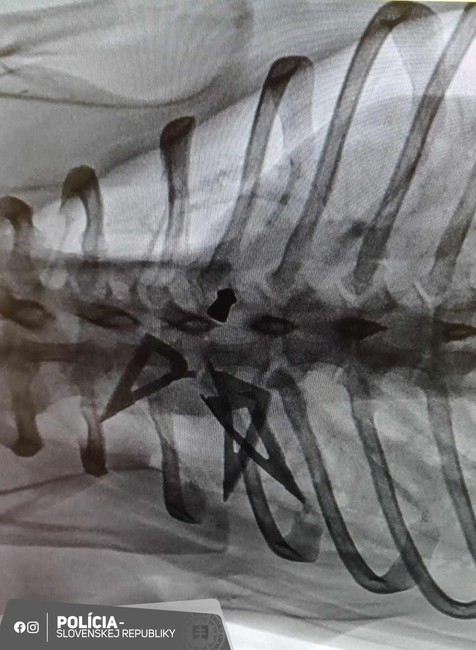

Páchateľ psíkovi spôsobil mu najmenej desať strelných rán vzduchovkou, malými športovými a loveckými šípmi v oblasti hlavy, tváre, dutiny brušnej a chrbta. "Jeden lovecký šíp po prejdení mäkkých tkanív prešiel cez hrudnú dutinu a narazil do stavca. Tým spôsobil trieštivú zlomeninu, ktorá mala za následok najvážnejšie zranenie zvieraťa," priblížila polícia.